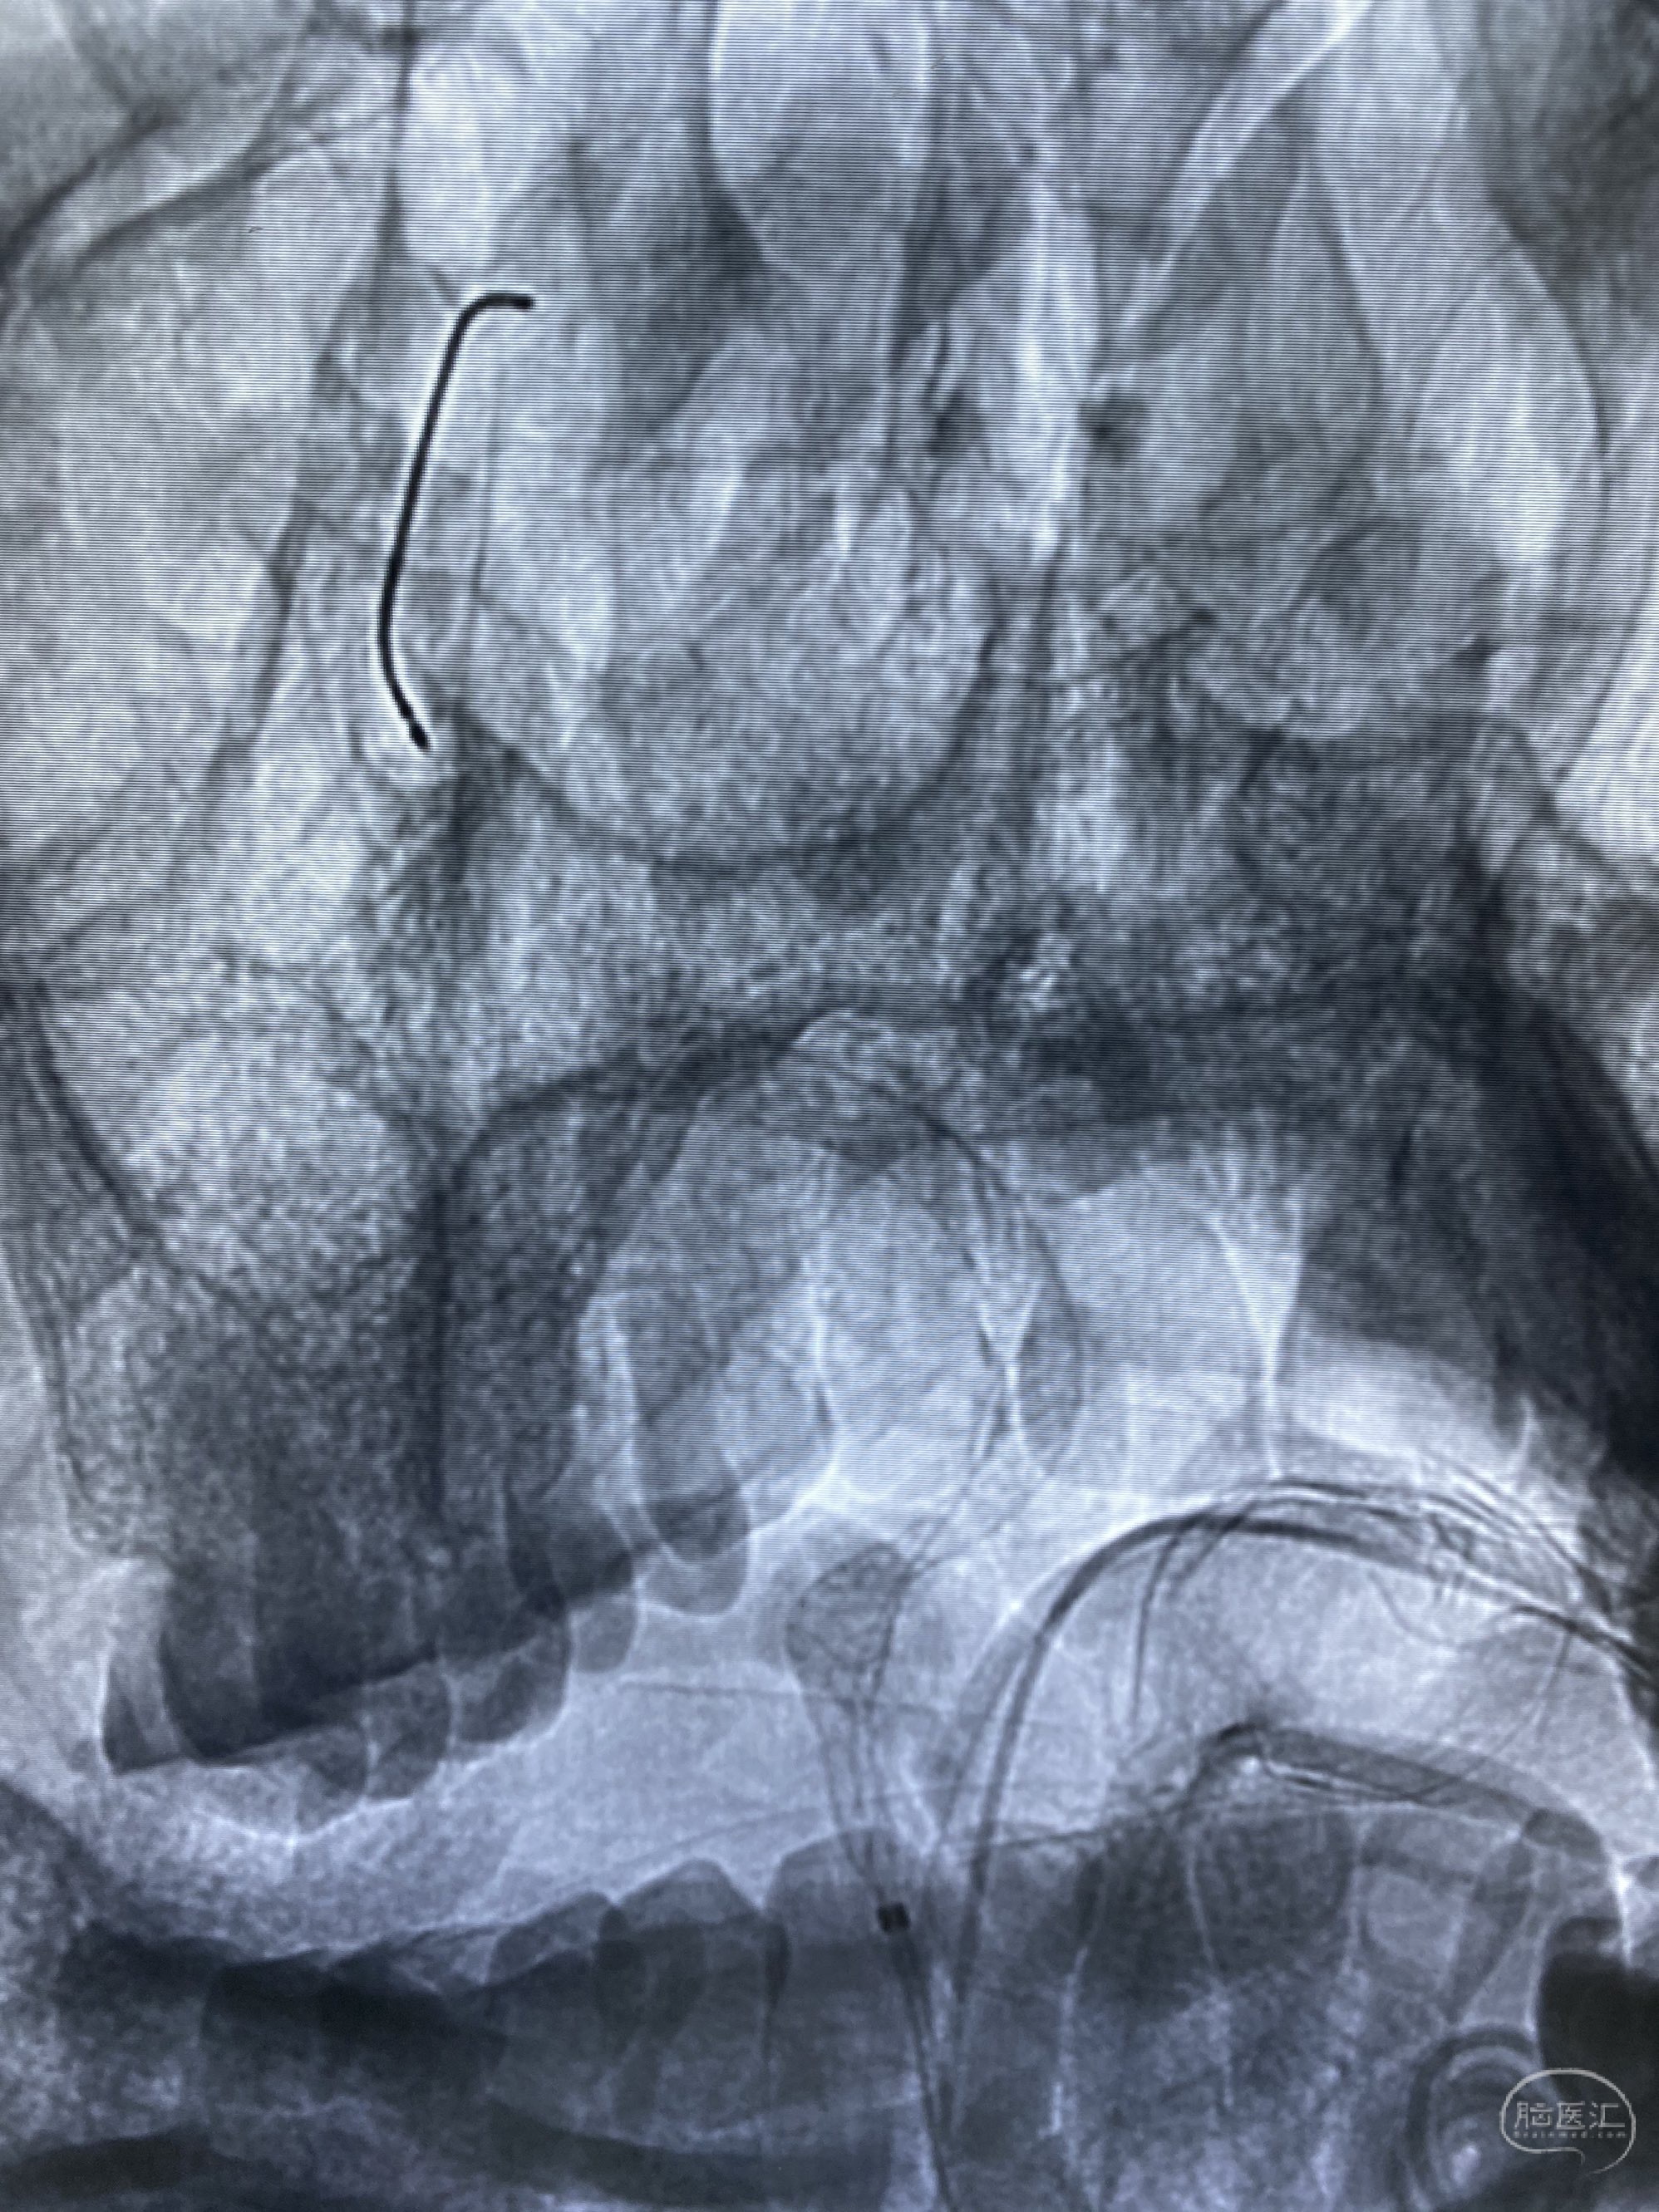

今日手术,TJG,M62Y,一期左侧颈动脉狭窄支架植入,二期椎动脉V4段多发夹层动脉瘤伴狭窄,常规支架辅助栓塞方法复杂又危险,血流导向装置植入快捷又安全。南阳市中心医院神经内科脑血管病介入团队pipeline flexFD植入两人导师资格。

椎动脉颅内段多发夹层动脉瘤伴载瘤动脉狭窄pipeline flex植入

今日手术,TJG,M62Y,一期左侧颈动脉狭窄支架植入,二期椎动脉V4段多发夹层动脉瘤伴狭窄,常规支架辅助栓塞方法复杂又危险,血流导向装置植入快捷又安全。南阳市中心医院神经内科脑血管病介入团队pipeline flexFD植入两人导师资格。